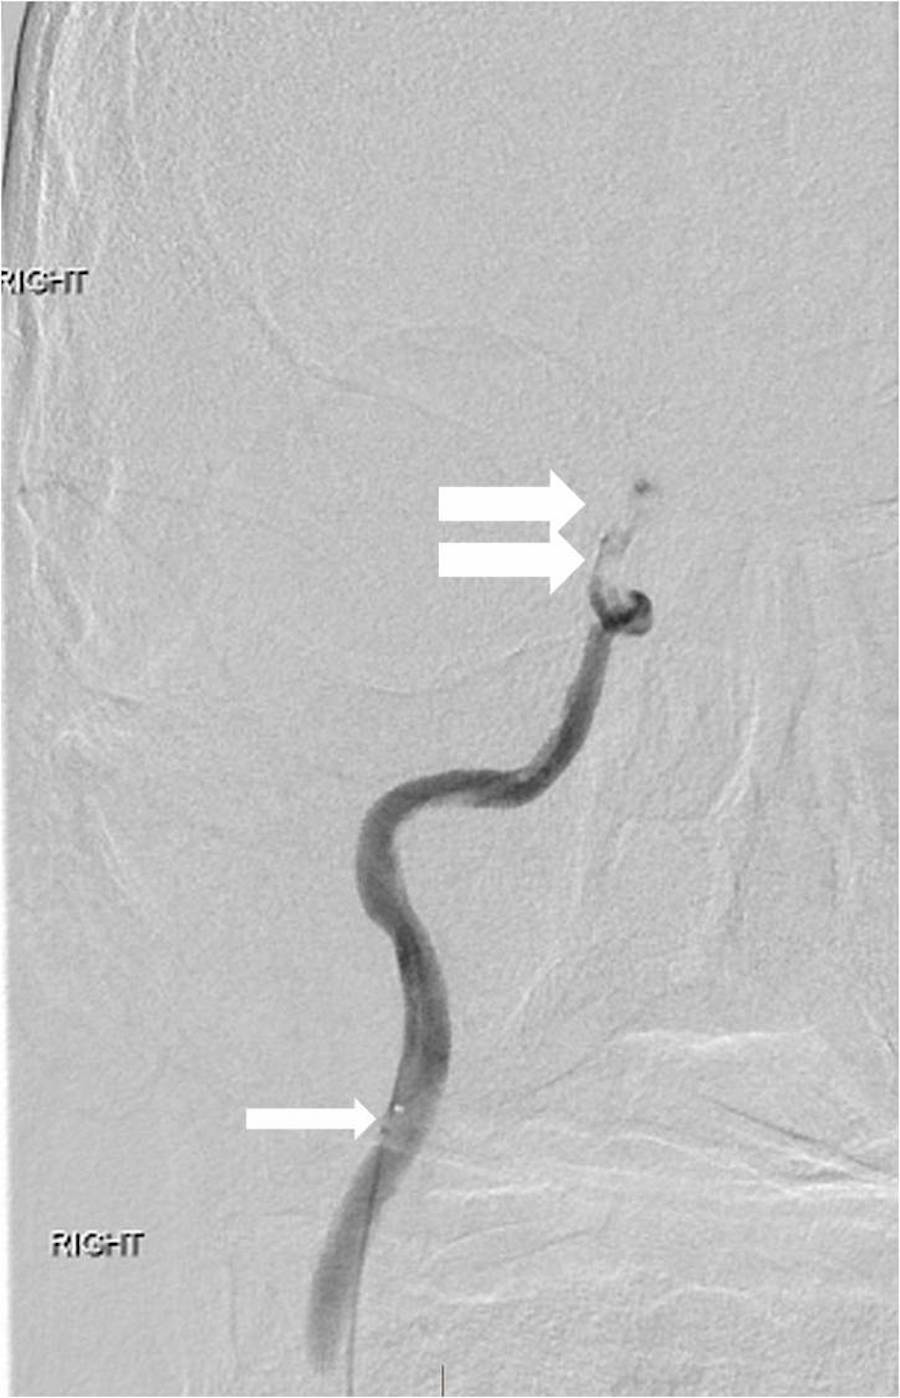

tPA was administered intravenously, and the patient was transferred to the interventional neuroradiology suite. Biplane digital subtraction angiography revealed a complete occlusion of the cervical right ICA at the vessel’s origin due to extensive atherosclerotic disease (Figure 6).

The right MCA and right anterior cerebral arteries (ACAs) could not be visualized, and multifocal embolic filling defects were detected within the cavernous and supraclinoid ICA segments on microcatheter contrast injection past the carotid origin occlusion (Figure 7).